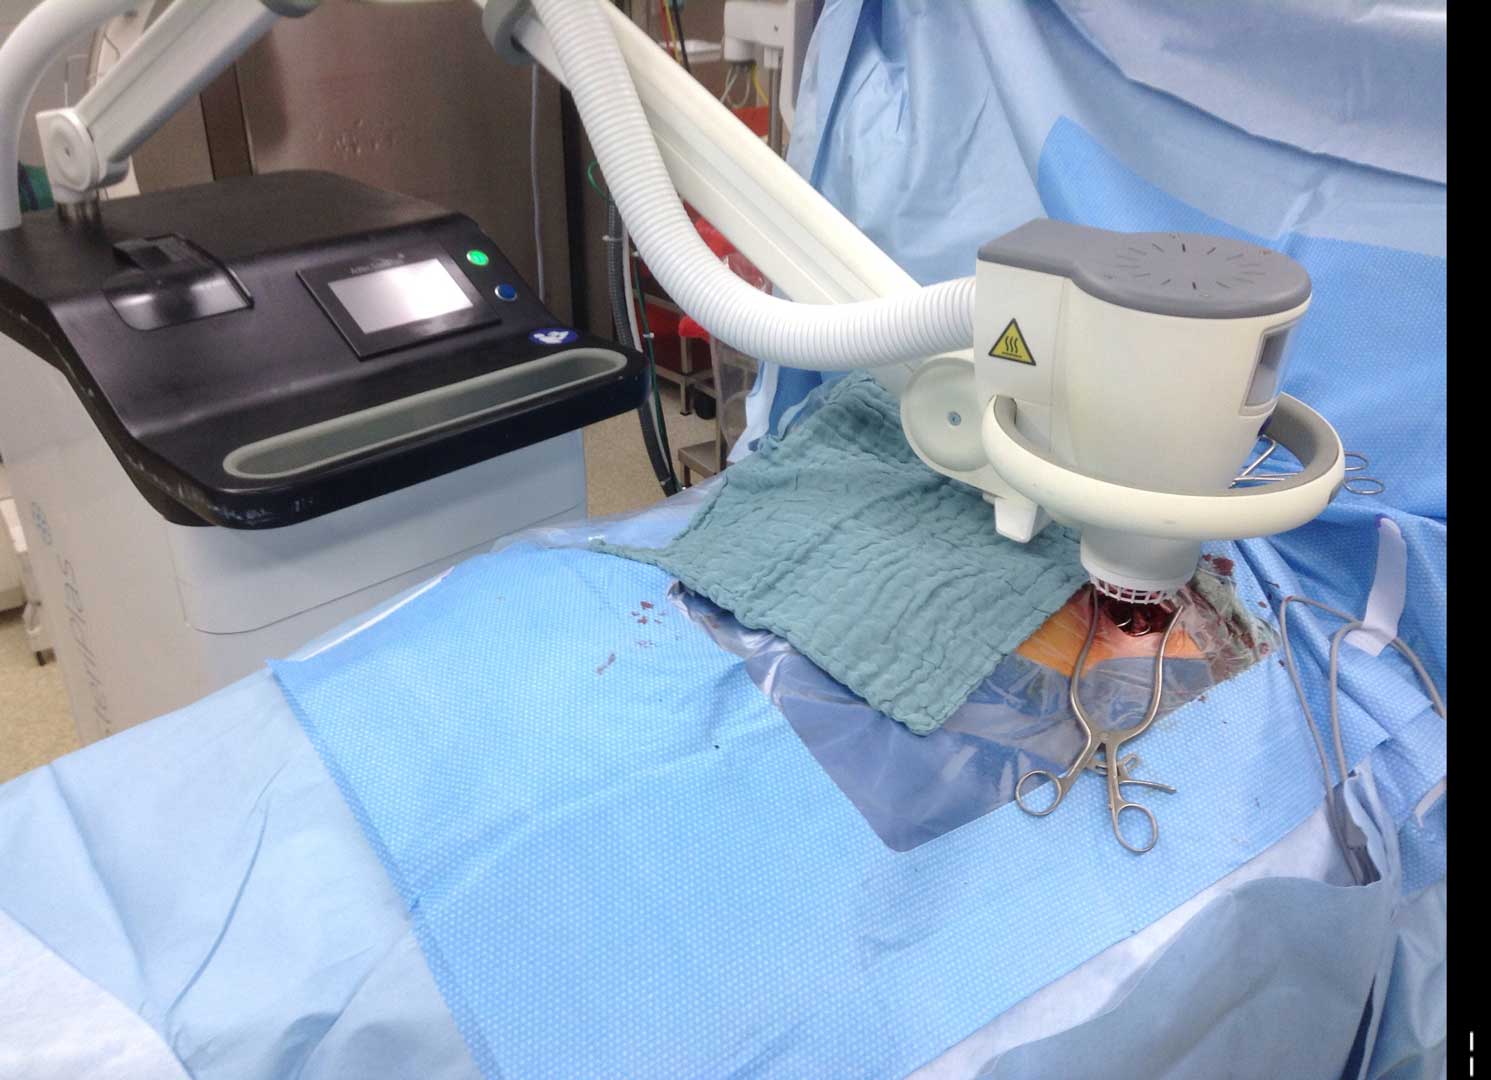

LVAD Driveline Infections

Infected LVAD drivelines may show recalcitrance to treatment with antibiotics and antimicrobial dressings. Antimicrobial dressings are unable to wrap the around infected driveline towards the source of biofilm.

Using the SteriPlas for the treatment of surgical site infections has shown remarkable results in accelerated healing. The gas plasma produced can penetrate through the gaps in crevices around the infected driveline reaching towards the source of biofilm where the bacteria is then destroyed using a physical mode of action.

Deep sternum infections are also very complex cardiac wound infections as a result of heart surgery. The mortality rate of patients with sternum infections are relatively high. The SteriPlas has been documented as a tissue and life saving approach to treating these complex wounds, eliminating the need for omentum majus or muscle flap plastic surgery. Treatment with the SteriPlas has shown to accelerate healing in problematic and stalled deep sternum infections or LVAD infections that are complicated with biofilm. The treatment is also well tolerated with no side effects being reported.